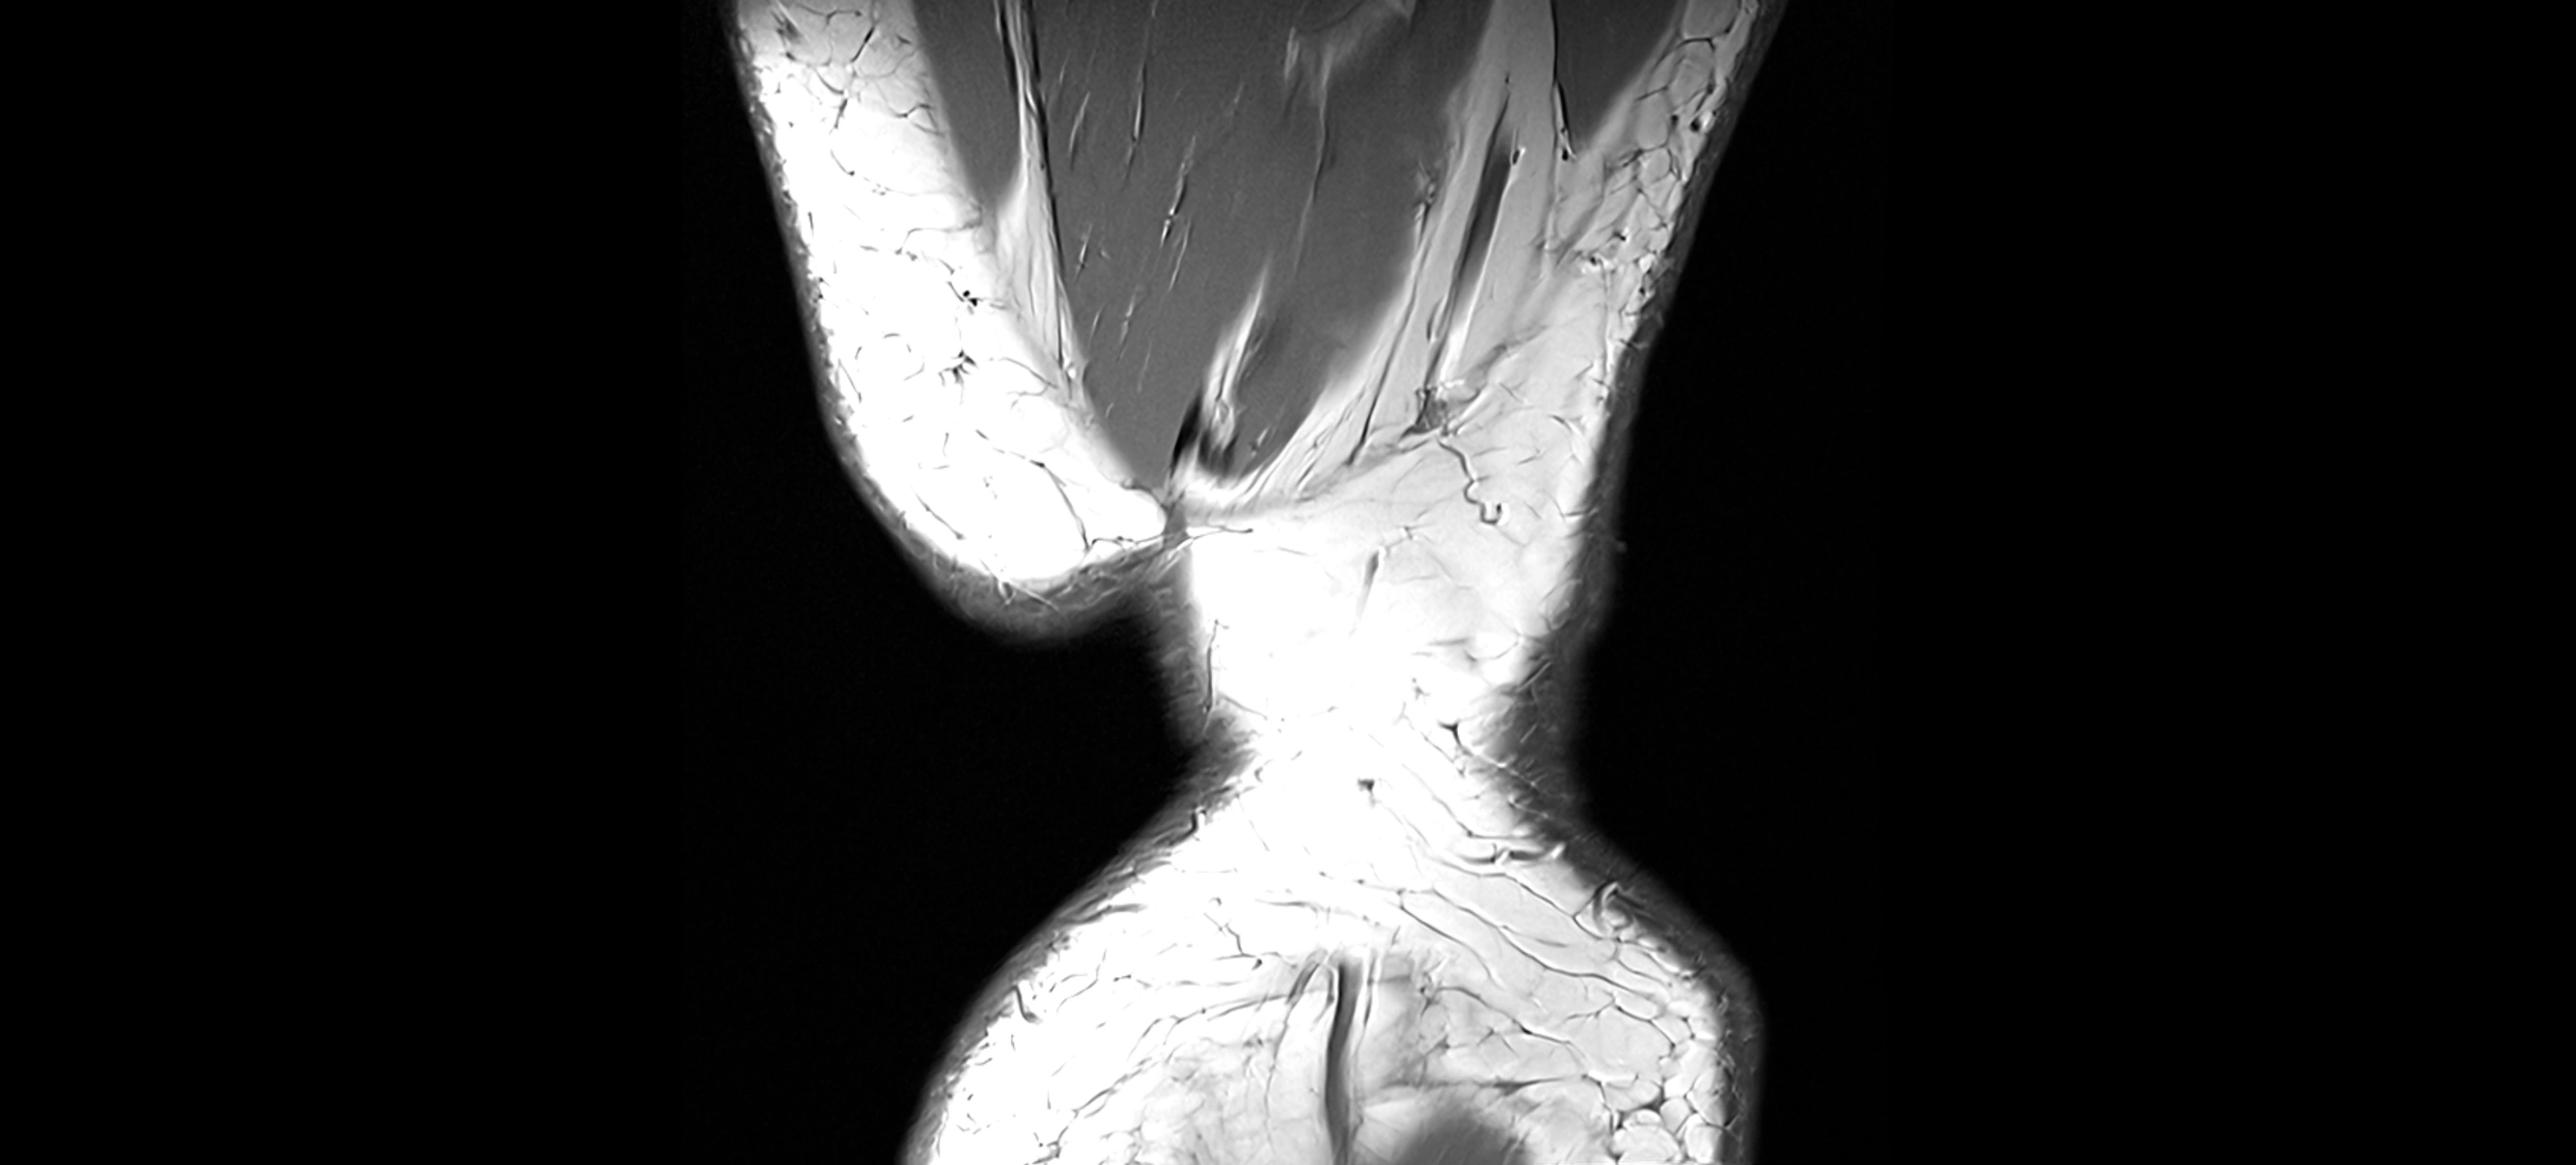

CT Appearance

Non-Contrast CT:

• ACL is not well visualized directly

• Can assess bony landmarks, intercondylar notch morphology, and tibial eminence fractures associated with ACL injury

Post-Contrast CT (CT Arthrography):

• Contrast outlines joint structures

• May demonstrate indirect signs of ACL tear (contrast leaking into abnormal spaces, displaced meniscus, or widened intercondylar notch)

• 3D CT reconstructions useful for pre-surgical planning of ACL reconstruction

CT image

image